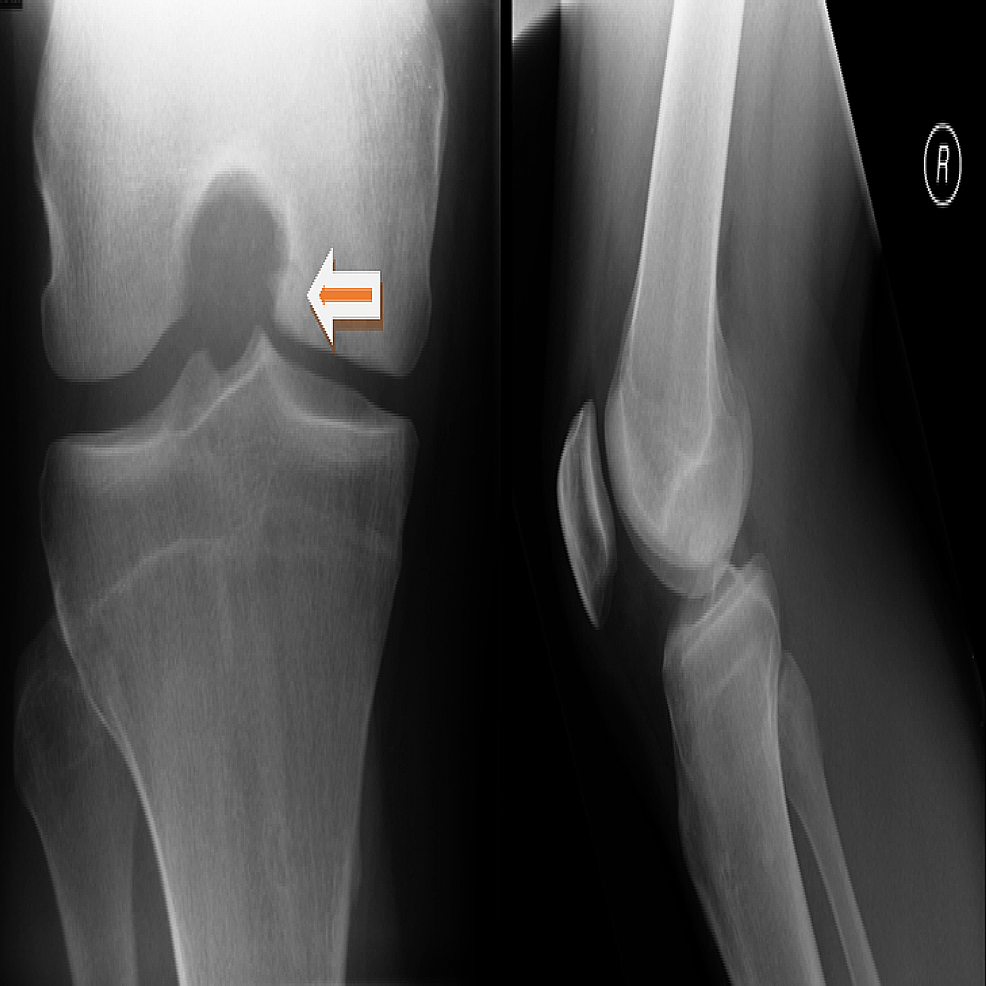

Arthroscopic Management of Isolated Tibial Plateau Defect With Microfracture and Micronized Arthroscopic Knee Surgery Microfracture This will help prevent knee arthritis. The goal of microfracture is to stimulate the growth of new articular cartilage by creating a new blood supply. Is microfracture surgery still a viable option for cartilage repair in modern orthopedics? This article addresses common questions about microfracture surgery,. Knee microfracture surgery is an arthroscopic surgical procedure to restore full thickness cartilage defects. Arthroscopic Knee Surgery Microfracture.

Cureus Microfracture Technique for Chronic Unstable Osteochondral Defect of Knee Case Report Arthroscopic Knee Surgery Microfracture Knee microfracture surgery is an arthroscopic surgical procedure to restore full thickness cartilage defects of the knee. The procedure can be done with an arthroscope. Is microfracture surgery still a viable option for cartilage repair in modern orthopedics? It is an arthroscopic procedure using a. The goal of this surgery is to prevent or slow further damage to the cartilage.. Arthroscopic Knee Surgery Microfracture.

Figure 1 from Clinical Efficacy of the Microfracture Technique for Articular Cartilage Repair in Arthroscopic Knee Surgery Microfracture The goal of this surgery is to prevent or slow further damage to the cartilage. This is performed most often in the knee (it can be used in the elbow, hip, ankle and other joints as well). A sharp tool called an awl is. Is microfracture surgery still a viable option for cartilage repair in modern orthopedics? It can help. Arthroscopic Knee Surgery Microfracture.

Arthroscopic Microfracture Treatment for Osteonecrosis of the Knee Arthroscopy Arthroscopic Knee Surgery Microfracture The procedure can be done with an arthroscope. The goal of this surgery is to prevent or slow further damage to the cartilage. Microfracture (mfx) is a marrow stimulation technique achieved by subchondral bone perforation to recruit autologous. A sharp tool called an awl is. Is microfracture surgery still a viable option for cartilage repair in modern orthopedics? The goal. Arthroscopic Knee Surgery Microfracture.